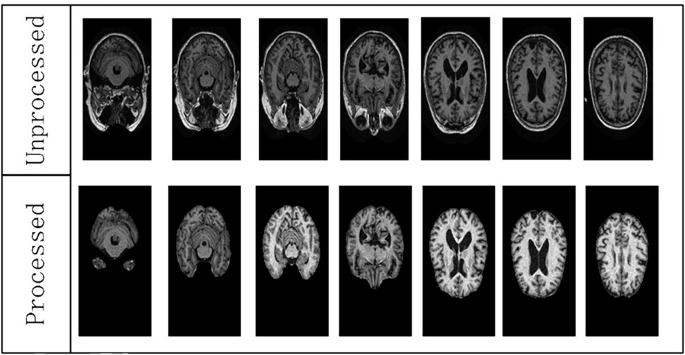

Regarding the lesion annotation function, the annotated images of CAGM are shown in Fig. 2. To verify the annotation accuracy of CAGM, we proposed three methods: multidimensional statistical analysis, heatmap validation (VFM), and atlas matching validation (AMV). Tumors and multiple sclerosis were introduced as additional independent datasets to validate the accuracy of the annotations.

a Non-demented unannotated control group. b1, b2 Very mild dementia, original and annotated images. c1, c2 Mild dementia original and annotated images. d Moderate dementia original and annotated images, e NondDem, f mild cognitive impairment, g Alzheimer’s disease, h early mild cognitive impairment, m late mild cognitive impairment, n Significant memory concern.

Presents a comparative example of manual annotations by clinicians and automatic annotations generated by CAGM, highlighting key brain anatomical structures (regions of atrophy or abnormal enlargement) as follows: 1 is R. cingulate gyrus, 2 is L. cingulate gyrus, 3 is R. superior parietal gyrus, 4 is R. pre-cuneus, 5 is L. pre-cuneus, 6 is L. cingulate gyrus, 7 is R. lateral ventricle, 8 is third ventricle, 9 is R. transverse temporal, 10 is R. superior temporal gyrus, 11 is L. superior temporal gyrus, 12 is Bilateral Hippocampus, 13 is R. parahippocampal gyrus, and 14 is L. parahippocampal gyrus. This comparison enables a visual evaluation of the consistency and potential discrepancies in CAGM annotations across cortical and subcortical structures, serving as a reference for subsequent quantitative analysis.